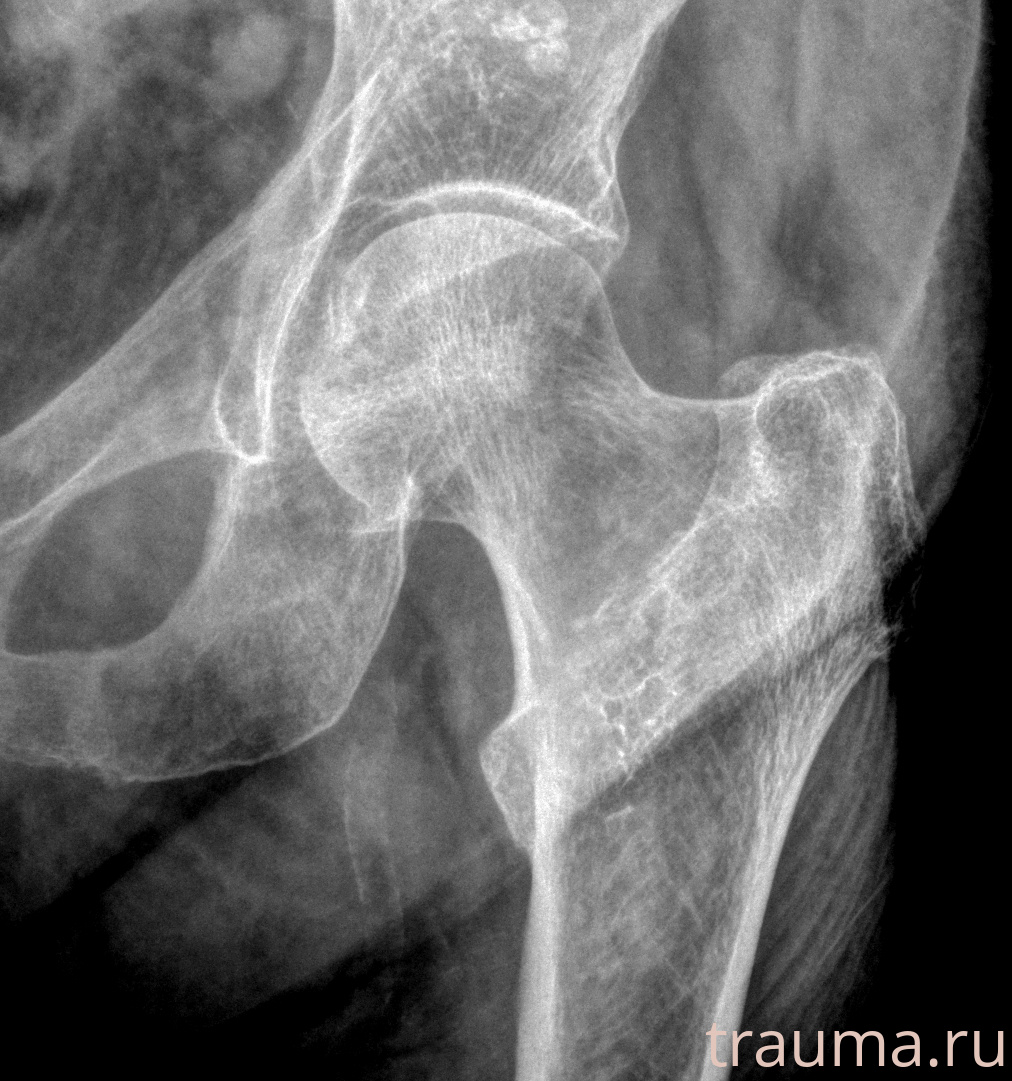

Рентгенограммы

Рентген на дому: по вашему адресу приезжает врач-рентгенолог, травматолог-ортопед с мобильным рентгеновским аппаратом, проводит диагностику травмы или заболевания, делает необходимые рентгенограммы, дает рекомендации по дальнейшему лечению. Получить качественные снимки в домашних условиях возможно благодаря уникальной методике, разработанной МосРентген Центром для института  Склифосовского

при переломе шейки бедра и пневмонии от компании МосРентген Центр - партнера Института имени Склифосовского